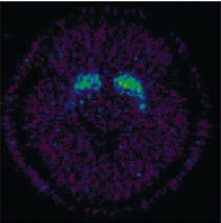

![]() |

The 11C-raclopride binding potential images at the level of the striatum for one participant during meditation (above) and during the speech (below). 11C-raclopride binding potential in ventral striatum is evidence of increase endogenous dopamine release during meditation.

According to the results, there was a significant decrease (7.9%) in BP in the ventral striatum. During active meditation, the participants reported a significant decrease in their readiness for action (p<0.05) along with heightened sensory imagery (p<0.05).

"The major finding of the present study has been the demonstration of increased dopaminergic tone in the ventral striatum during an altered conscious state...the fact that the ventral striatum was the only region in which the decrease in dopamine receptor availability reached statistical significance is of interest. Two of the three front-subcortical circuits regulating behavior include structures in the ventral striatum," the authors explained.